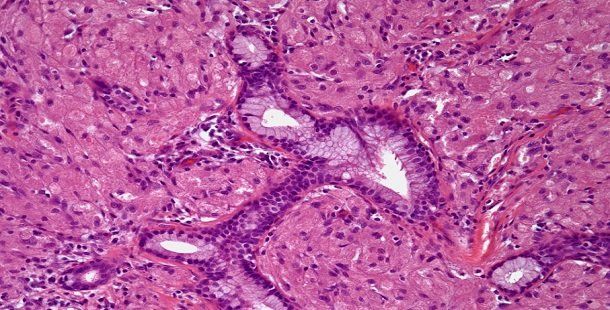

A 76-year-old man is found to have a right upper lobe mass. After further evaluation, a biopsy is performed. What is your diagnosis?